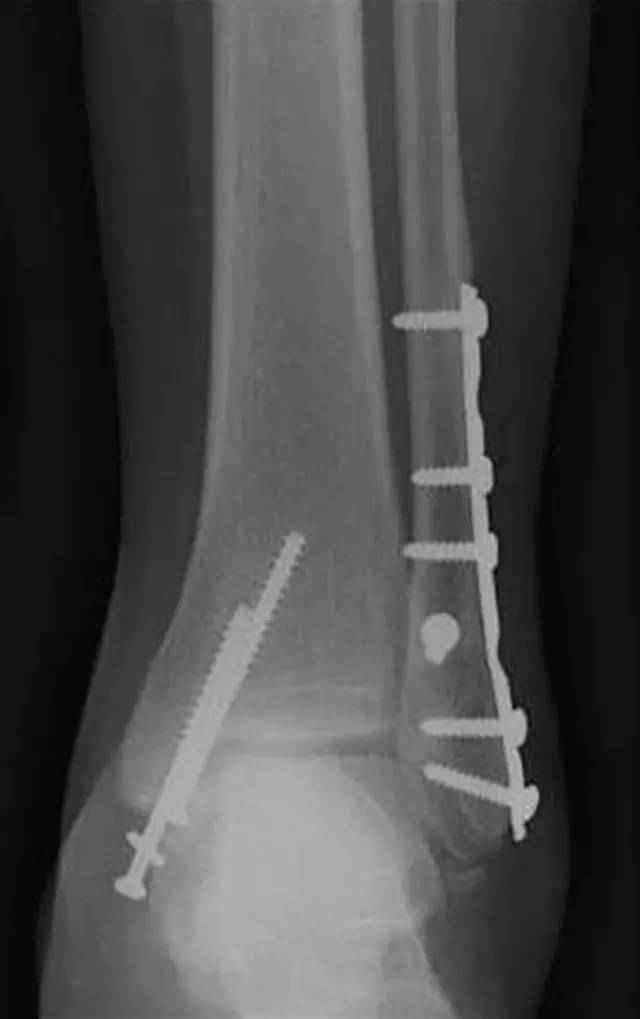

典型的垂直型骨折

内踝内收型损伤,关节面存在塌陷,这是一种严重的损伤,术中需要复位塌陷的关节面。

内踝垂直型骨折的手术技巧